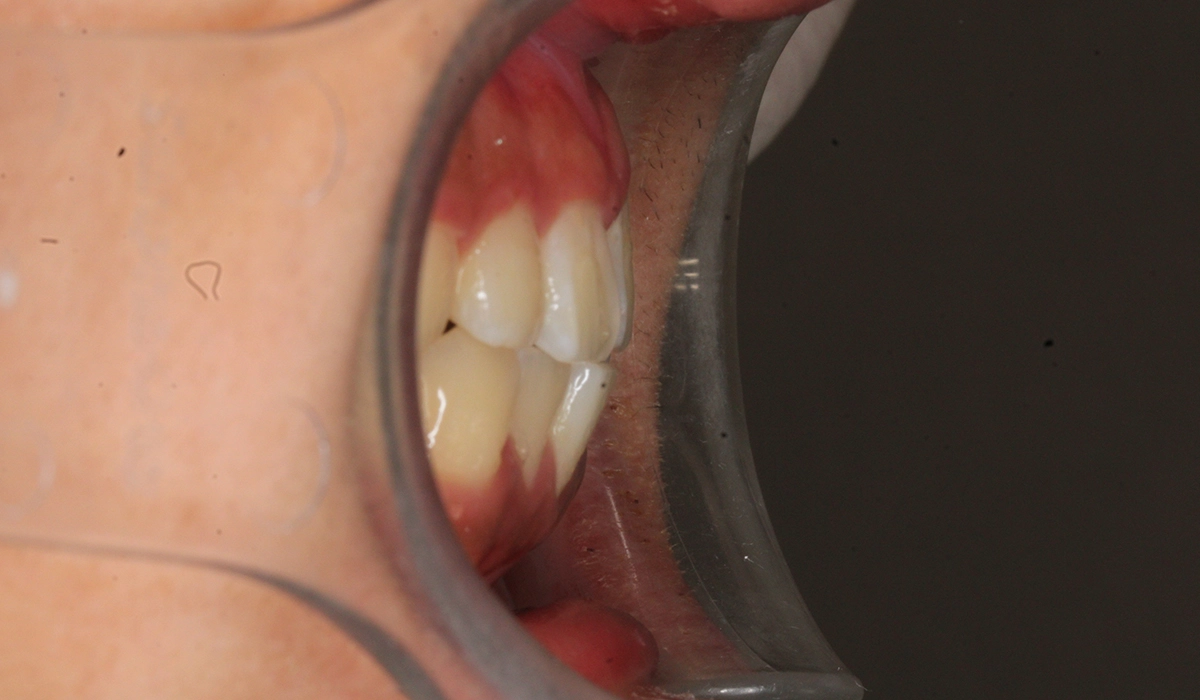

術前:右側